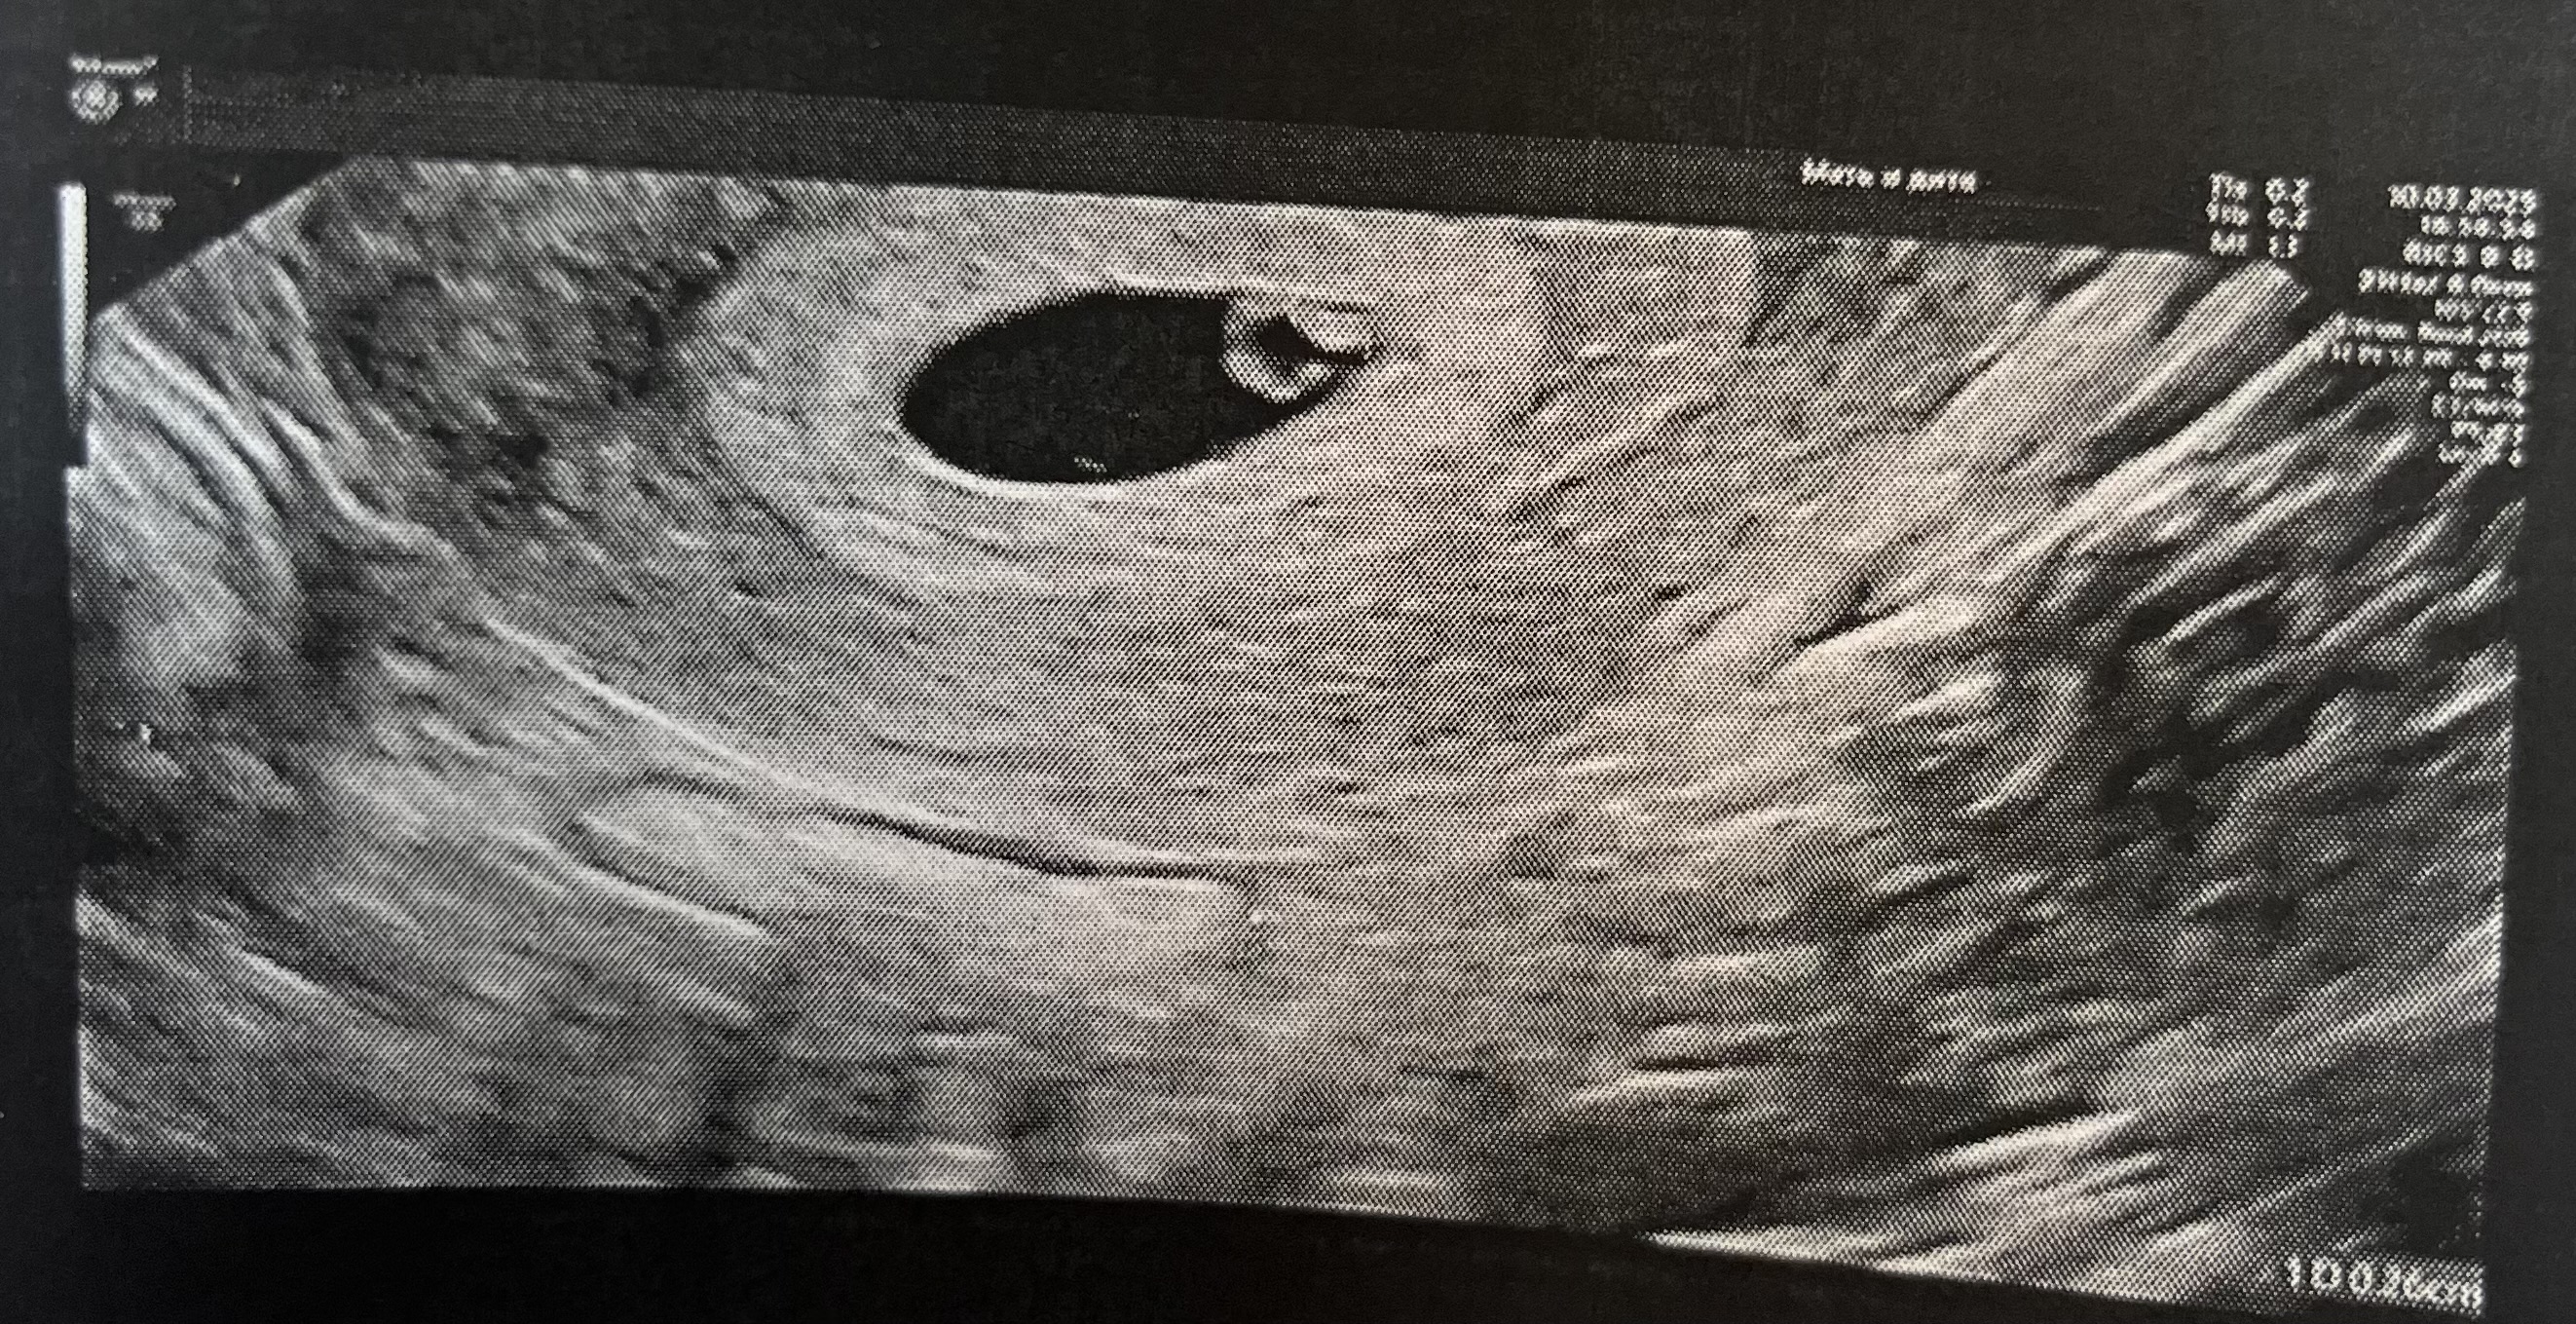

Расти малыш - первое УЗИ 21 дпп

Результаты УЗИВот и дождалась свое первое УЗИ 🥹

Плодное яйцо 12,7 мм, КТР 3 мм. Пока сердцебиения нет, сказали еще рано, нужно слушать через неделю. Вроде все хорошо 🥹 Тревожно, подташнивает, болит грудь, температура иногда поднимается до 37-37.3, настроение скачет. Простыла недавно еще, температура 38 была, сбивала парацетамолом, больше слава богу не поднималась..

Иду на повторное узи и на прием к ре 18.03